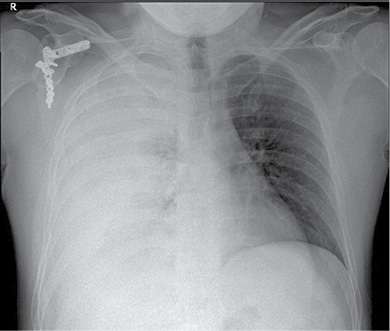

36 m. vyras P. D. atvyko į Gastroenterologijos skyrių patikslinti diagnozės planine kepenų biopsija. Praėjus 8 val. po procedūros, pacientas pajuto maudimą po dešiniuoju šonkaulių lanku punkcijos vietoje. Apžiūros metu pacientas buvo hemodinamiškai stabilus. Atlikus laboratorinius tyrimus, nustatyta saiki anemizacija (hemoglobinas – 128 g/l; norma – 135–160 g/l). Įtariant kraujavimą pilvaplėvėje, atlikta pilvo echoskopija: pilvo ertmėje laisvo skysčio nematyti, dešinėje pleuroje iki 4 cm laisvo skysčio ruožas. Konsultuota krūtinės chirurgo. Rekomenduota atlikti krūtinės ląstos rentgenogramą (Ro). Nustatytas beveik neoringas dešinysis plautis, pastebėta hidrotorakso požymių (1 pav.). Įtarus jatrogeninį hemotoraksą, krūtinės chirurgas atliko diagnostinę pleuros punkciją. Patvirtinus hemotorakso diagnozę, drenuota dešinė pleuros ertmė, išsiskyrė 400 ml kraujo. Tuo metu aktyvaus kraujavimo nenustatyta, hemodinamika išliko stabili, kartotiniuose laboratoriniuose tyrimuose – saiki anemizacija (hemoglobinas – 120 g/l). Atlikus kontrolinę rentgenogramą, nustatytas sumažėjęs skysčio kiekis pleuroje, buvo matyti kompresinių dešiniojo plaučio pakitimų. Įtariant sukrešėjusį hemotoraksą, atlikta skubi krūtinės ląstos KT (2 pav.), kuri patvirtino įtariamą patologiją. Tolesniam operaciniam gydymui pacientas perkeltas į Krūtinės chirurgijos skyrių. Atlikta skubi VATS (angl. video assisted thoracoscopic surgery). Operacijos metu pašalinta 1 000 ml krešulių, aktyvaus kraujavimo nenustatyta, diafragmos kupole rasta nedidelė hematoma. Pooperacinis periodas sklandus (3 pav.). Po trijų dienų geros būklės pacientas išleistas į namus.

2 pav. Krūtinės ląstos KT atlikus pleuros ertmės drenavimą (prieš operaciją)